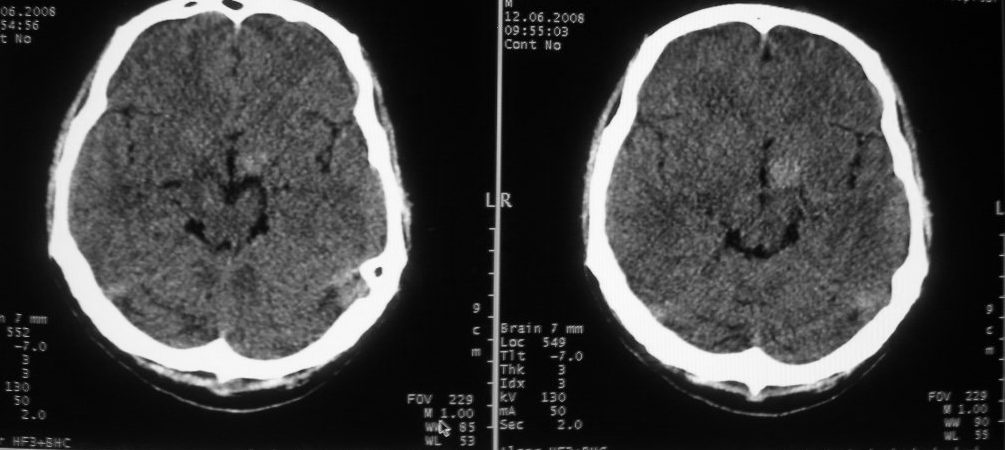

以下是引用守望可可西里在2008-6-13 1:25:00的发言:[br][br] 1.双侧大脑中动脉高密度踌型样接近于全程显示,部分大脑前动脉、基底动脉也呈高密度改变。[br] 2.右侧基底节多发类圆形ct值接近于出血的高密度,边缘模糊。双侧小脑幕及直窦、上矢状窦增宽、模糊。左侧横窦和乙状窦区密度增高、呈云雾状,内缘模糊。[br] 如果这样的表现发生在一个老年人脑部,我们首先会想到是高血压、动脉粥样硬化,就可以很容易得出结论。但这发生在一个20岁年青人的身上,且病程长达半年、临床症状不怎么重,这就比较蹊跷且应该引起高度重视了。[br] 我认为此病人应该是一个血液病患者--双侧大脑中动脉、部分大脑前动脉及基底动脉的高密度改变,只是一个假象:即相对于ct值偏低,只有35的脑灰质而言的相对高密度。而那么多出血改变,则是真正的病变表现。[br] 建议临床进一步进行其他相关的血液、骨髓检查,肝、脾也应该好好检查,应有明显的肿大。